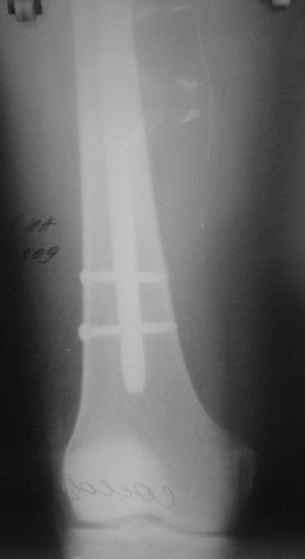

На голени что-то сделать с отломком вынуждает угроза перфорация кожи, перекрытие отломком входа в канал. Не всегда надо делать разрез, можно и шилом чрескожно фрагмент сдвинуть. Наверно, еще и повреждение сосудистого пучка, когда "виновник" прямо поперек перерезанной артерии и лежит - такое не каждый за всю свою профессиональную жизнь

встретит.

То есть в представленных ситуациях при штифтовании ни на бедре, ни на голени не нужно делать ни открытую, ни закрытую (с помощью шильев,

спиц, еще каких-то "джойстиков") репозицию. Все, что нужно - восстановить ось, длину и ротацию.

Перелом большеберцовой кости почти околосуставный, могут потребоваться дополнительные меры для восстановления оси (отклоняющие спицы или винты), и запирающих винтов в дистальный отломок желательно побольше. Задний край не сломан ли там, не разобрал по этим снимкам.